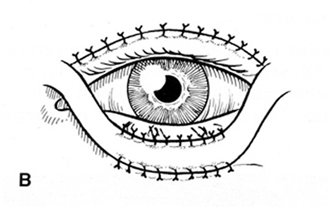

Una vez corregida la laxitud horizontal, desplazamos el colgado bi pediculado de su lecho dador, al receptor en el parpado inferior. (Figura 5)

Figura 5 Colgajo en su lecho receptor

La piel que queda junto a la hendidura palpebral, comprendida entre la incisión sub ciliar inferior y la del pliegue del parpado superior, en sus extremos agudos nasal y temporal queda completamente libre ,flotante. Procedemos a acomodar el colgajo en tal forma que estos extremos agudos nasal y temporal, de la hendidura palpebral se desplacen hacia arriba, que asciendan como si se tratara de una Z plastia, quedando colocados mas altos que en su sitio original, al trasponer sobre ellos los pedículos laterales del colgajo.

Procedemos luego a practicar una sutura única continua con un Nylon 6-00 ,que comienza en el extremo temporal de la incisión superior, fijando el extremo agudo temporal de piel de la hendidura, al ángulo superior del colgajo. Se desliza luego la sutura sobre todo el parpado superior, igual que en una blefaroplastia, hasta llegar al extremo nasal, cuando nuevamente se busca el ángulo agudo de piel de la hendidura para ascenderlo a su nueva posición mas alta, transponiendo el pedículo del colgajo.

Suturamos luego la incisión sub ciliar, que corresponde a la superior del colgajo en su lecho, llevándola de del canto medio al externo y al llegar al extremo temporal nos devolvemos nuevamente al nasal, en donde rematamos la sutura continua con un punto final. La piel que queda en el parpado superior desde la base de la ceja a las pestañas, no debe tener menos de 2cm.